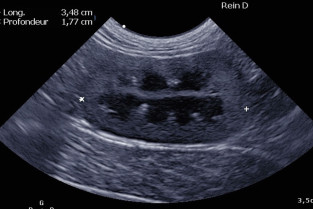

Les Ateliers du Sud-Est abordent cette année le thème de l'uro-néphrologie chez le chien et le chat.

Des conférenciers enthousiastes sélectionnés par le bureau de l'AFVAC Sud-Est aborderont l'uro-néphrologie dans différents domaines (médecine interne, nutrition, urgences et soins intensifs, chirurgie, oncologie et comportement) sous un angle adapté à notre pratique au quotidien.

- dépister, explorer et gérer une insuffisance rénale aigüe, une insuffisance rénale chronique et proposer une alimentation adaptée ;

- dépister, explorer et gérer les tumeurs de l'appareil urinaire et néphrologique ;

- connaître et pratiquer les différents gestes techniques possibles en uro-néphrologie ;

- pratiquer et interpréter un examen de cytologie urinaire ;